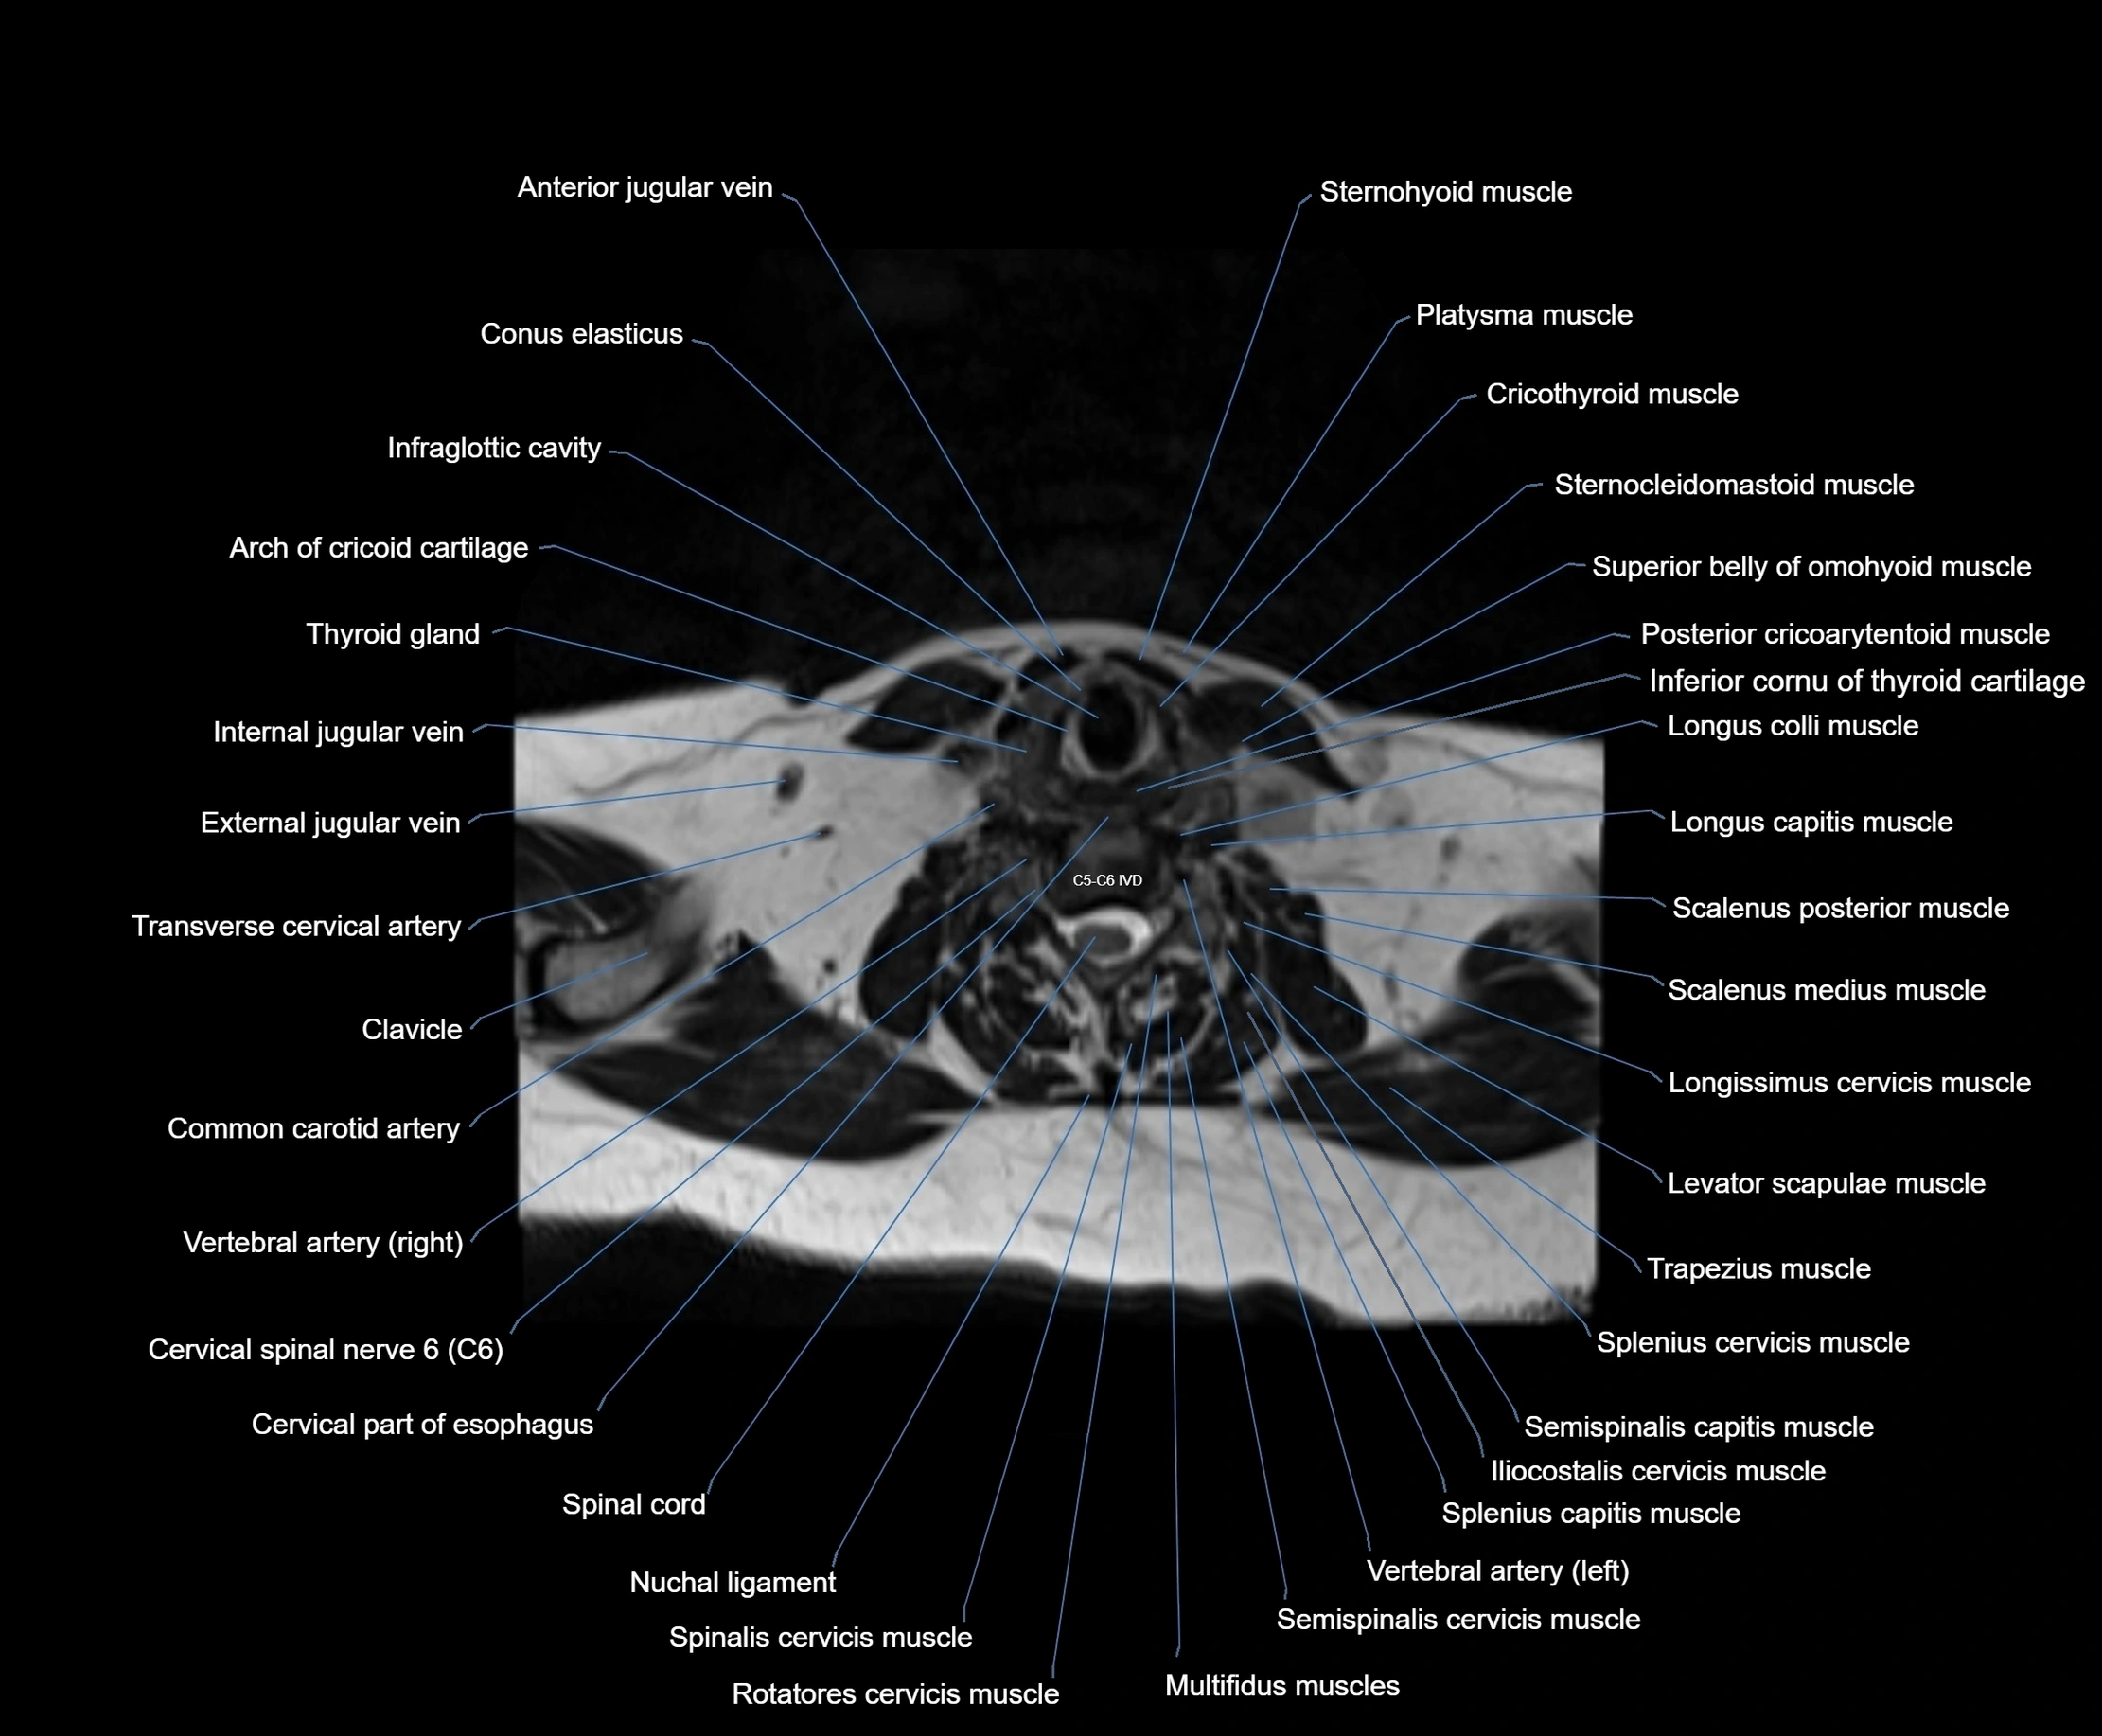

- Arch of cricoid cartilage

- Cervical part of esophagus

- Cervical spinal nerve 6 (C6)

- Clavicle

- Common carotid artery

- Conus elasticus

- Cricothyroid muscle

- External jugular vein

- Inferior cornu of thyroid cartilage

- Infraglottic cavity

- Longissimus cervicis muscle

- Multifidus muscles

- Nuchal ligament

- Rotatores cervicis muscle

- Spinal cord

- Spinalis cervicis muscle

- Splenius cervicis muscle